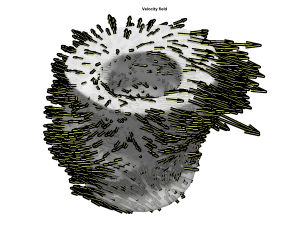

Fig. 5 demonstrates a 3D visualisation of the 3D velocity field from a full stack of TPM at peak expansion (a) before translational motion compensation, (c) after before translational motion compensation with method 1 and (b) method 2. The 3D visualisation of the uncorrected stack shows a bias in the velocity field caused by translational velocity, whereas the corrected stacks look more balanced. This visualisation of results pictures the difference in the two methods: Method 1 yields a stack which looks overall more symmetric as correction has been applied slice by slice taking into account the centre of mass per slice. On the other hand method 2 yields a stack where the base seems to move in opposite direction to the mid-wall and apex, revealing a relative motion between the lower and upper part of the LV. Visualisation of the second stack is looks more realistic and method 2 is recommended when examining deformation from the entire volume. When looking at deformation slice by slice method 1 yields more intuitive results and it is recommended in that case.